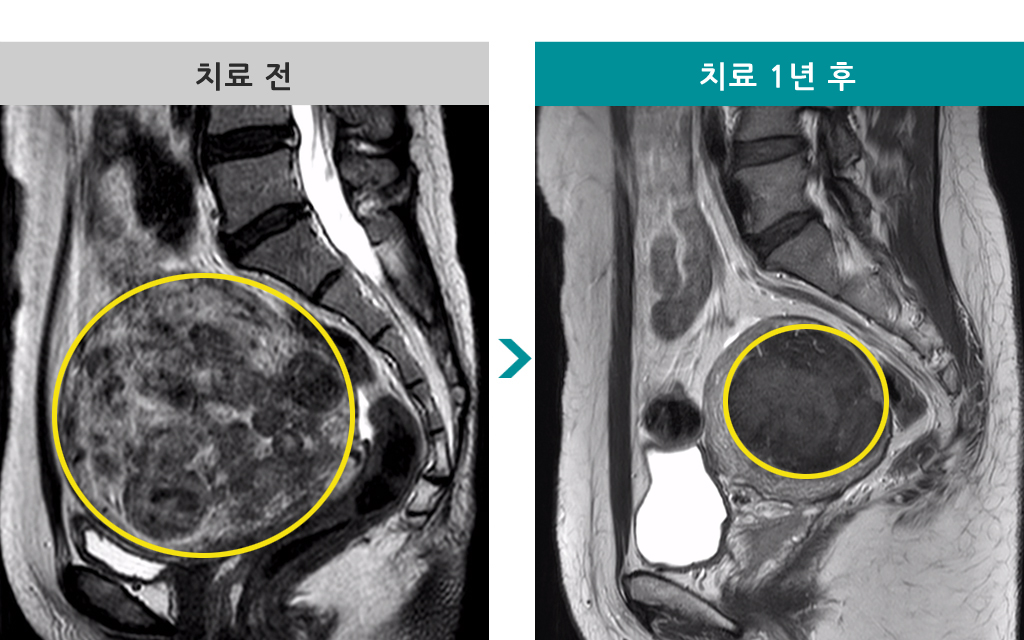

49세 [자궁근종 색전술] 전후 MRI사진 비교